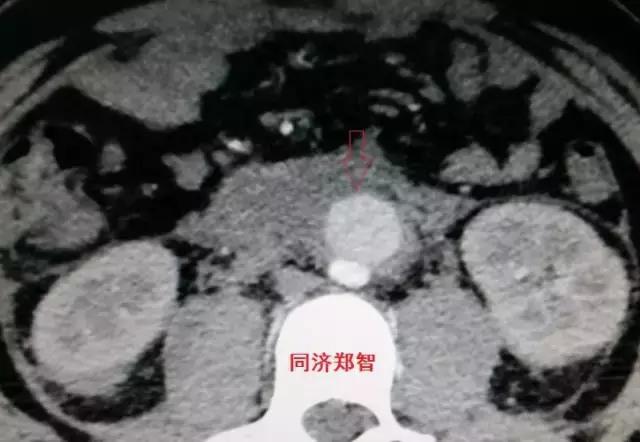

二

第二招 血管内膜征

正常情况下,主动脉的血管内膜在平扫CT中无法识别,但在某些特殊情况下,主动脉夹层及主动脉壁间血肿的平扫CT中也可以显示,从而帮助诊断。

病例五

平扫CT提示主动脉弓层面及右肺动脉层面均可见主动脉血管腔内的内膜片影(红色箭头所示),CTA显示为A型主动脉夹层。